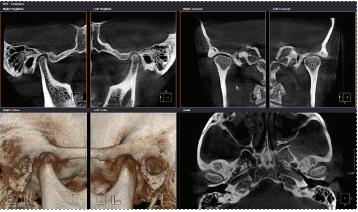

The RAYSCAN Studio integrates CBCT, 3D Face and CT impression (intraoral data) scan into a perfect imaging machine. You can provide effective and predictable treatment planning and transfer CBCT data to a 3D printing system for rapid production of dental appliances.

CBCT

- Max 20 x 20 Light Guided FOV

- Scan Time 4.9 - 16 Seconds